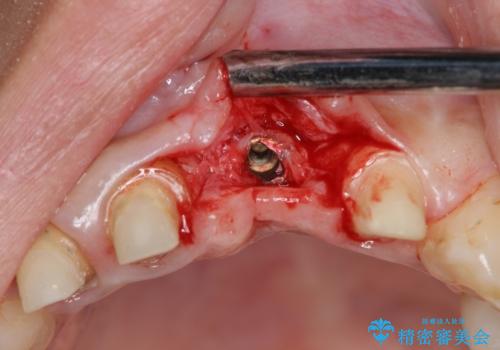

不良インプラントを除去し最終的にブリッジによる補綴で審美性の改善を行うこと、その準備として骨の造成・歯肉の移植による歯の欠損部顎堤のボリュームを維持・増大を計画します。

感染したインプラントからは排膿が間欠的に認められ、掻爬・除去が検討されうるような状況でした。

より審美的な改善を強く求められたため、インプラントを除去し可及的に欠損部顎堤を増大したのちブリッジによる審美改善を行いました。